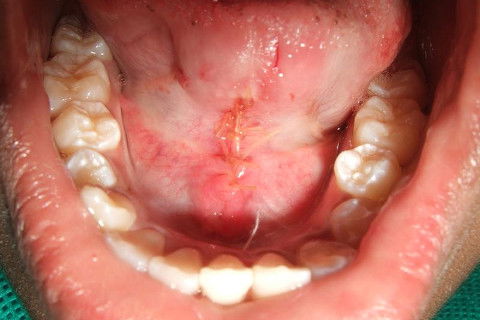

REMOVIDO O FREIO

COM A SUTURA FOI UTILIZADO CAT GUT